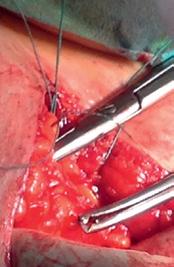

Tratament chirurgical

Tratamentul chirurgical constă în histerectomie totală cu anexectomie bilaterală, cu recomandarea de a fi efectuat pe cale minim invazivă, atunci când resursele materiale și experiența chirurgului o permit. Stadializarea ganglionară este recomandată și ea se face prin identificarea și excizia ganglionului santinelă, atunci când imagistica (IRM) nu indică semne evidente de metastaze ganglionare. Limfadenectomia este recomandată în cazurile de risc intremediar înalt sau risc înalt. În USA limfadenectomia este recomandată și în cazurile de tumori > 2 cm, invazie miometrială > 50%, G3, sau histologie specială (seroasă sau celulă clară). Omentectomia este recomandată în cazul carcinoamelor seroase.